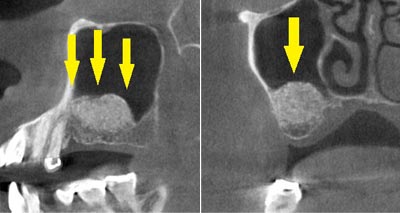

CTで見ると、骨が薄いのが良く分かります。黄色の矢印の部分、白く写るのが骨で、矢印のある黒い部分が上顎洞という空洞です。

CTで見ると、骨が薄いのが良く分かります。黄色の矢印の部分、白く写るのが骨で、矢印のある黒い部分が上顎洞という空洞です。

この空洞部分に、人工骨を入れて、閉鎖しておくと、数か月ほどで骨に置き代わっていき、インプラントを埋入できるだけの骨量になります。サイナスリフトが終了して、数か月経過し、薄かった骨が十分な厚みができたCT画像です。黄色矢印の部分、白く写る骨が増えています。

この空洞部分に、人工骨を入れて、閉鎖しておくと、数か月ほどで骨に置き代わっていき、インプラントを埋入できるだけの骨量になります。サイナスリフトが終了して、数か月経過し、薄かった骨が十分な厚みができたCT画像です。黄色矢印の部分、白く写る骨が増えています。